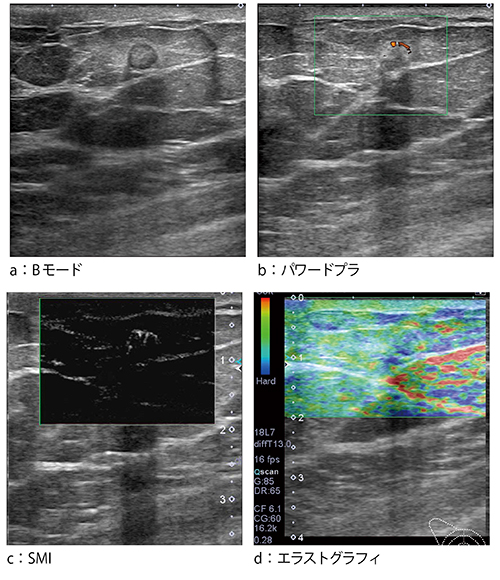

●症例1:浸潤性乳管癌(31歳)

症例1は,超音波検診にて右乳房に腫瘤性病変が指摘された。Bモードでは,乳腺の中に認められる腫瘤で,後方エコーが増強していた(図3 a)。パワードプラでは,腫瘤は比較的大きいものの,中を貫くような血流がうまく描出されず,血流が不連続に点在していた(図3 b)。しかし,SMIでは,腫瘤の内部へと続く連続した血流が明瞭に描出されている(図3 c)。SMIは白黒表示だけでなく,カラー表示も可能である(図3 d)。SMIを適用することで,従来見えなかった血流が見えるようになったとの印象を持った。

図3 症例1:浸潤性乳管癌(31歳)